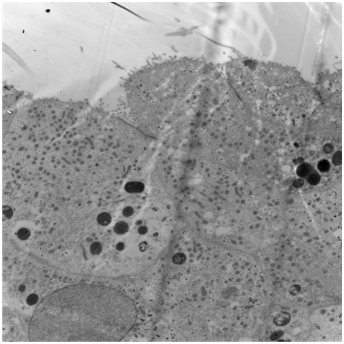

No melanocytes were visible on routine staining with haematoxylin and eosin or with the immunoperoxidase stain S100 or with electron microscopy. The urothelium was not dysplastic. Some areas had metaplastic changes of cystitis cystica. The pigment was negative with Perl’s and with periodic acid Schiff (PAS) stains, excluding haemosiderin and lipofuscin respectively. Masson stain was positive, and bleaching removed the pigment, together indicating that the pigment was melanin. Electron microscopy showed that the pigment was bound in lysosomes and that there were no melanosomes (Figure 4). The final histopathological diagnosis was melanosis of the urinary bladder.

However, the presence of melanocytes, usually characterized by positivity to immunoperoxidase stains such as S-100 and / or HMB-45 was not consistently observed in all the reported cases. No concurrent dysplasia or malignancy was seen in any of these cases. The demonstration of melanosis in the absence of melanocytes is the key feature in this case report. It appears that the urothelial cells have taken up melanin within lysosomes, rather than having it delivered to them via dendritic melanocytes, which is the usual process in normal skin, for example. The source of the pigment is unknown. The principal question raised in previous reports is whether melanosis of the bladder is essentially a benign condition or whether it is a pre-malignant harbinger of vesical malignant melanoma. The lack of melanocytes would suggest that this is a benign condition.